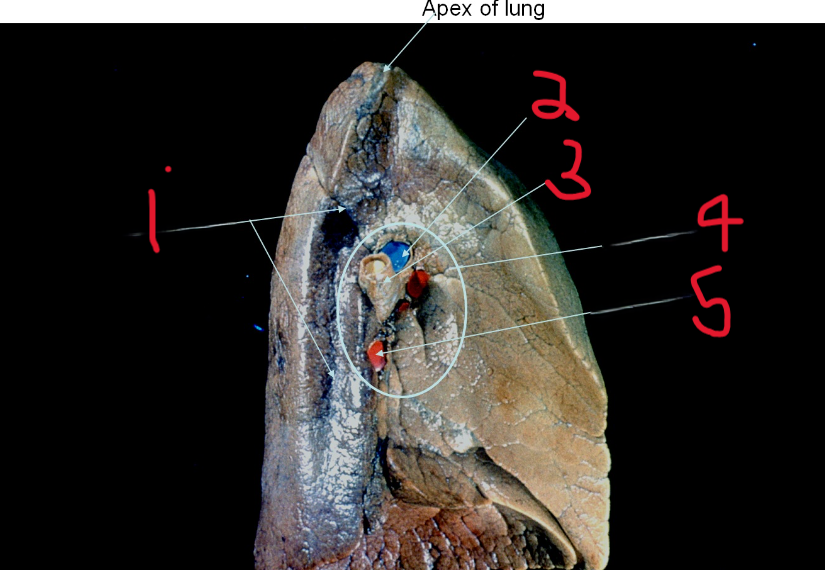

Aortic impression

What is depicted by #1

Pulmonary artery

What is depicted by #2

Left main bronchus

What is depicted by #3

Hilum of lung

What is depicted by #4

Pulmonary vein

What is depicted by #5